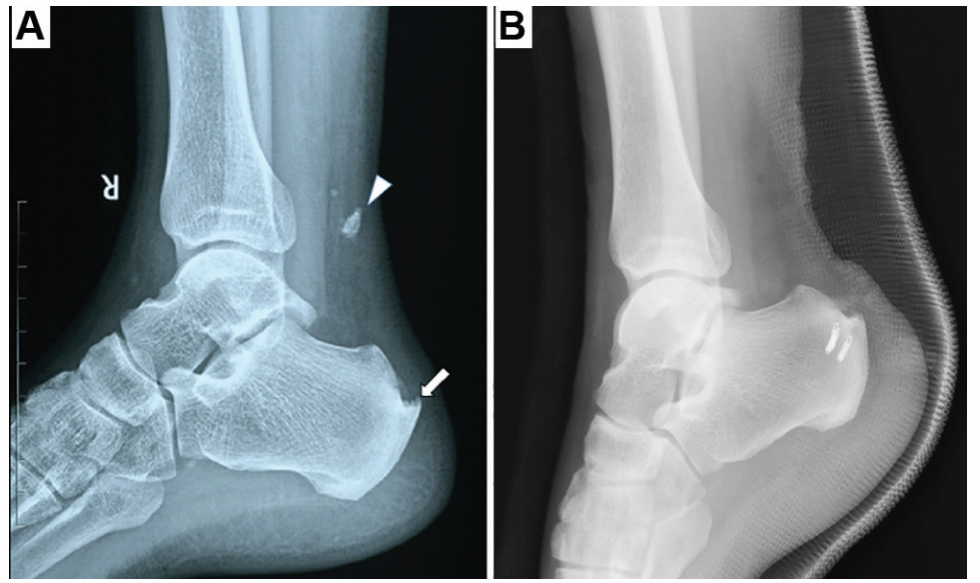

此外,专业组率先报道应用骨折块切除结合韧带止点修复的手术方法治疗外踝撕脱骨折,取得良好的临床疗效,并牵头多家单位制定中国外踝撕脱骨折的临床诊疗指南。专业组还提出跟腱止点重建治疗撕脱骨折的手术治疗方法;率先开展距下关节镜及距下关节韧带损伤的手术治疗;提出跟距骨桥的改良CT分型方法,指导关节镜下跟距骨桥切除手术,多种足踝运动创伤的诊疗水平均达到了国际领先水平。

图三 跟腱止点撕脱骨折

图四 双排止点重建治疗跟腱撕脱骨折